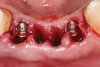

A 53-year-old male presented with localized advanced periodontal disease of the mandibular incisors. Teeth Nos. 23 to 26 exhibited Class II mobility because of advanced bone loss (Figure 1). The teeth had migrated out of position over the years, and a diastema had developed between No. 24 and No. 25 (Figure 2). The patient complained about the poor esthetic appearance of these teeth, and he was able to perceive their loss of strength on function as a result of their mobility.

Figure 1  Preoperative clinical condition.

Figure 1